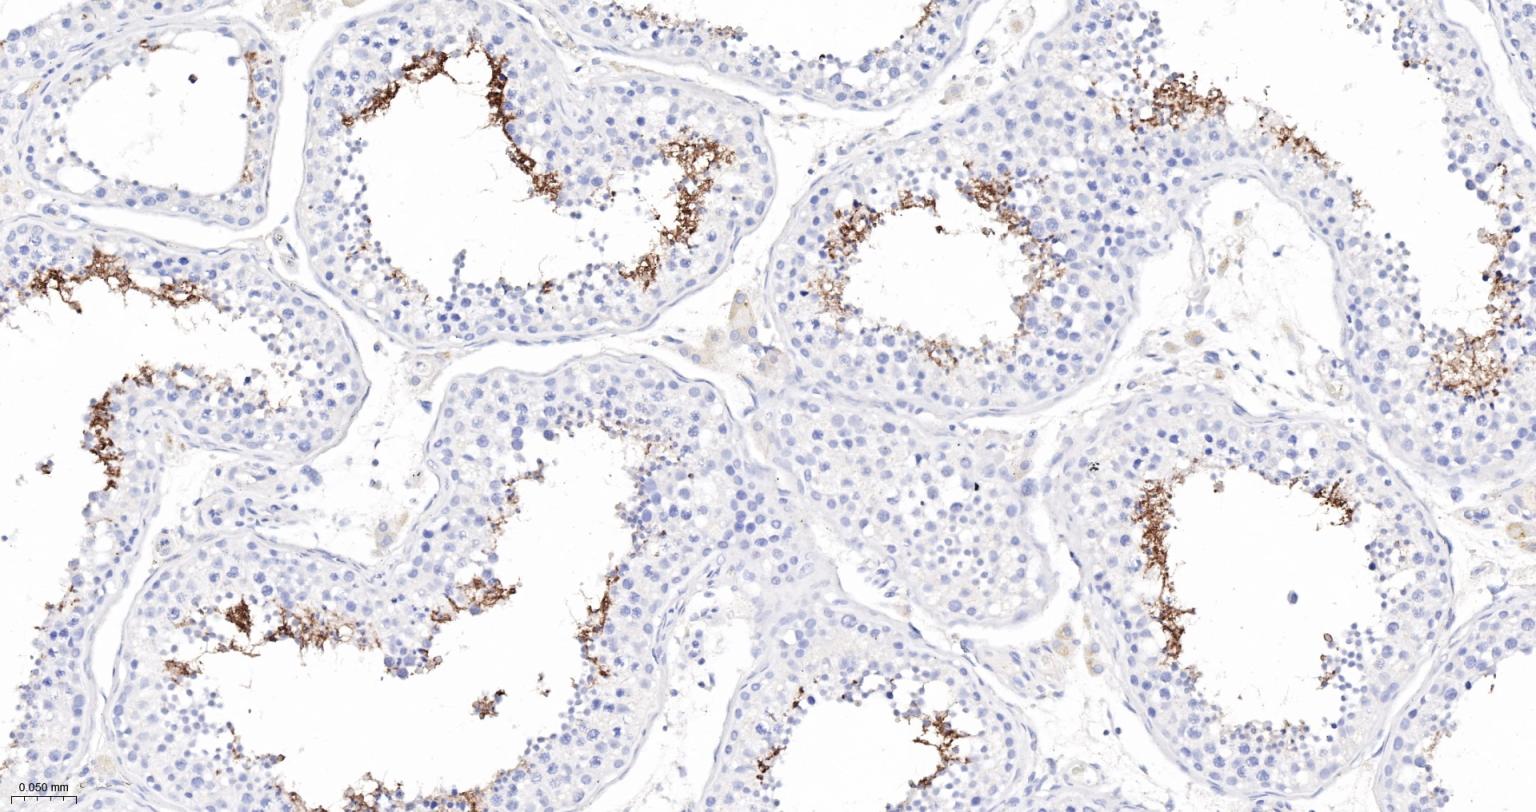

Paraformaldehyde-fixed, paraffin embedded Human Testicles; Antigen retrieval by boiling in sodium citrate buffer (pH6.0) for 15 min; The section was incubated with ACE Monoclonal Antibody, Unconjugated (bsm-61652R) at 1:200 overnight at 4°C, followed by conjugation to the bs-0295G-HRP and DAB (C-0010) staining.